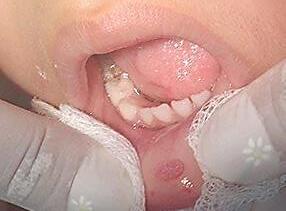

Presentación de caso clínico

Paciente femenino de 26 años presenta una lesión nodular de 0.5 cm. en borde lateral de la lengua de consistencia firme, color rosa pálido y asintomático.

Apareció hace dos años y desapareció con el tiempo, con recidiva hace un año. Al estudio de patología se observa epitelio escamoso estratificado

hiperparaqueratinizado con clavos

Fig. 2

Verruga Vulgar autoría propia vista microscópica

epiteliales elongados que tienden a converger hacia el centro, se observan coilocitos y células apoptóticas, el estroma

es de tejido conjuntivo laxo bien vascularizado, hacia la base; tejido muscular estriado. (Fig 2). Se diagnóstico como Verruga vulgar cavidad oral.

Después de entregar el diagnóstico de patología se recomienda seguimiento a largoplazo.

Nota:Fototomadaporelautor